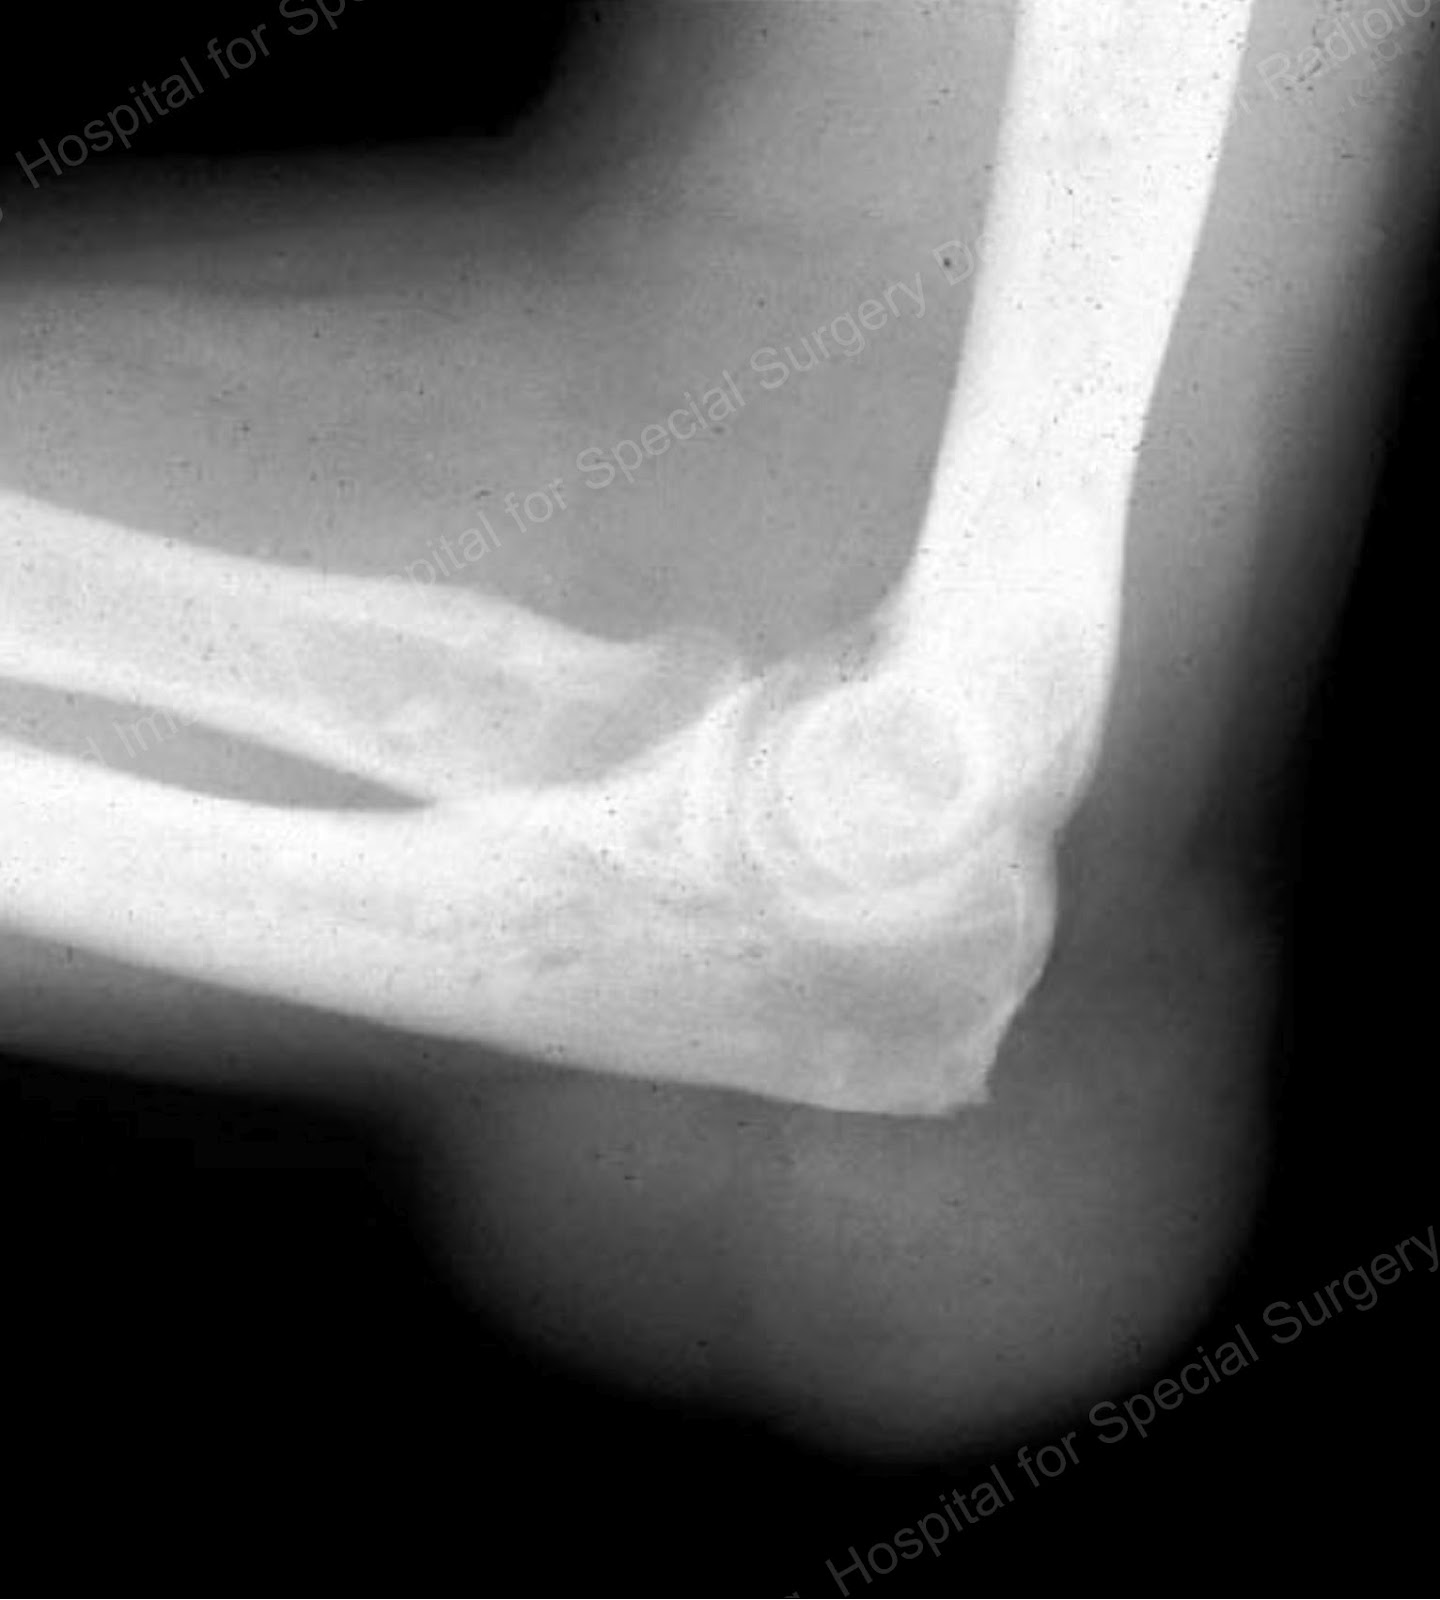

From www.researchgate.net

Tophaceous gout of the posterior elbow in 3 different patients. (a Can Gout Be In Elbows Symptoms of gout in the elbow can develop suddenly and cause intense pain. Medications and lifestyle changes can help reduce symptoms of gout in the elbow. Other commonly affected joints include the ankles, knees, elbows, wrists and fingers. Gout usually affects the big toe, but it can occur in any joint. Currently, there is no cure for gout in the. Can Gout Be In Elbows.